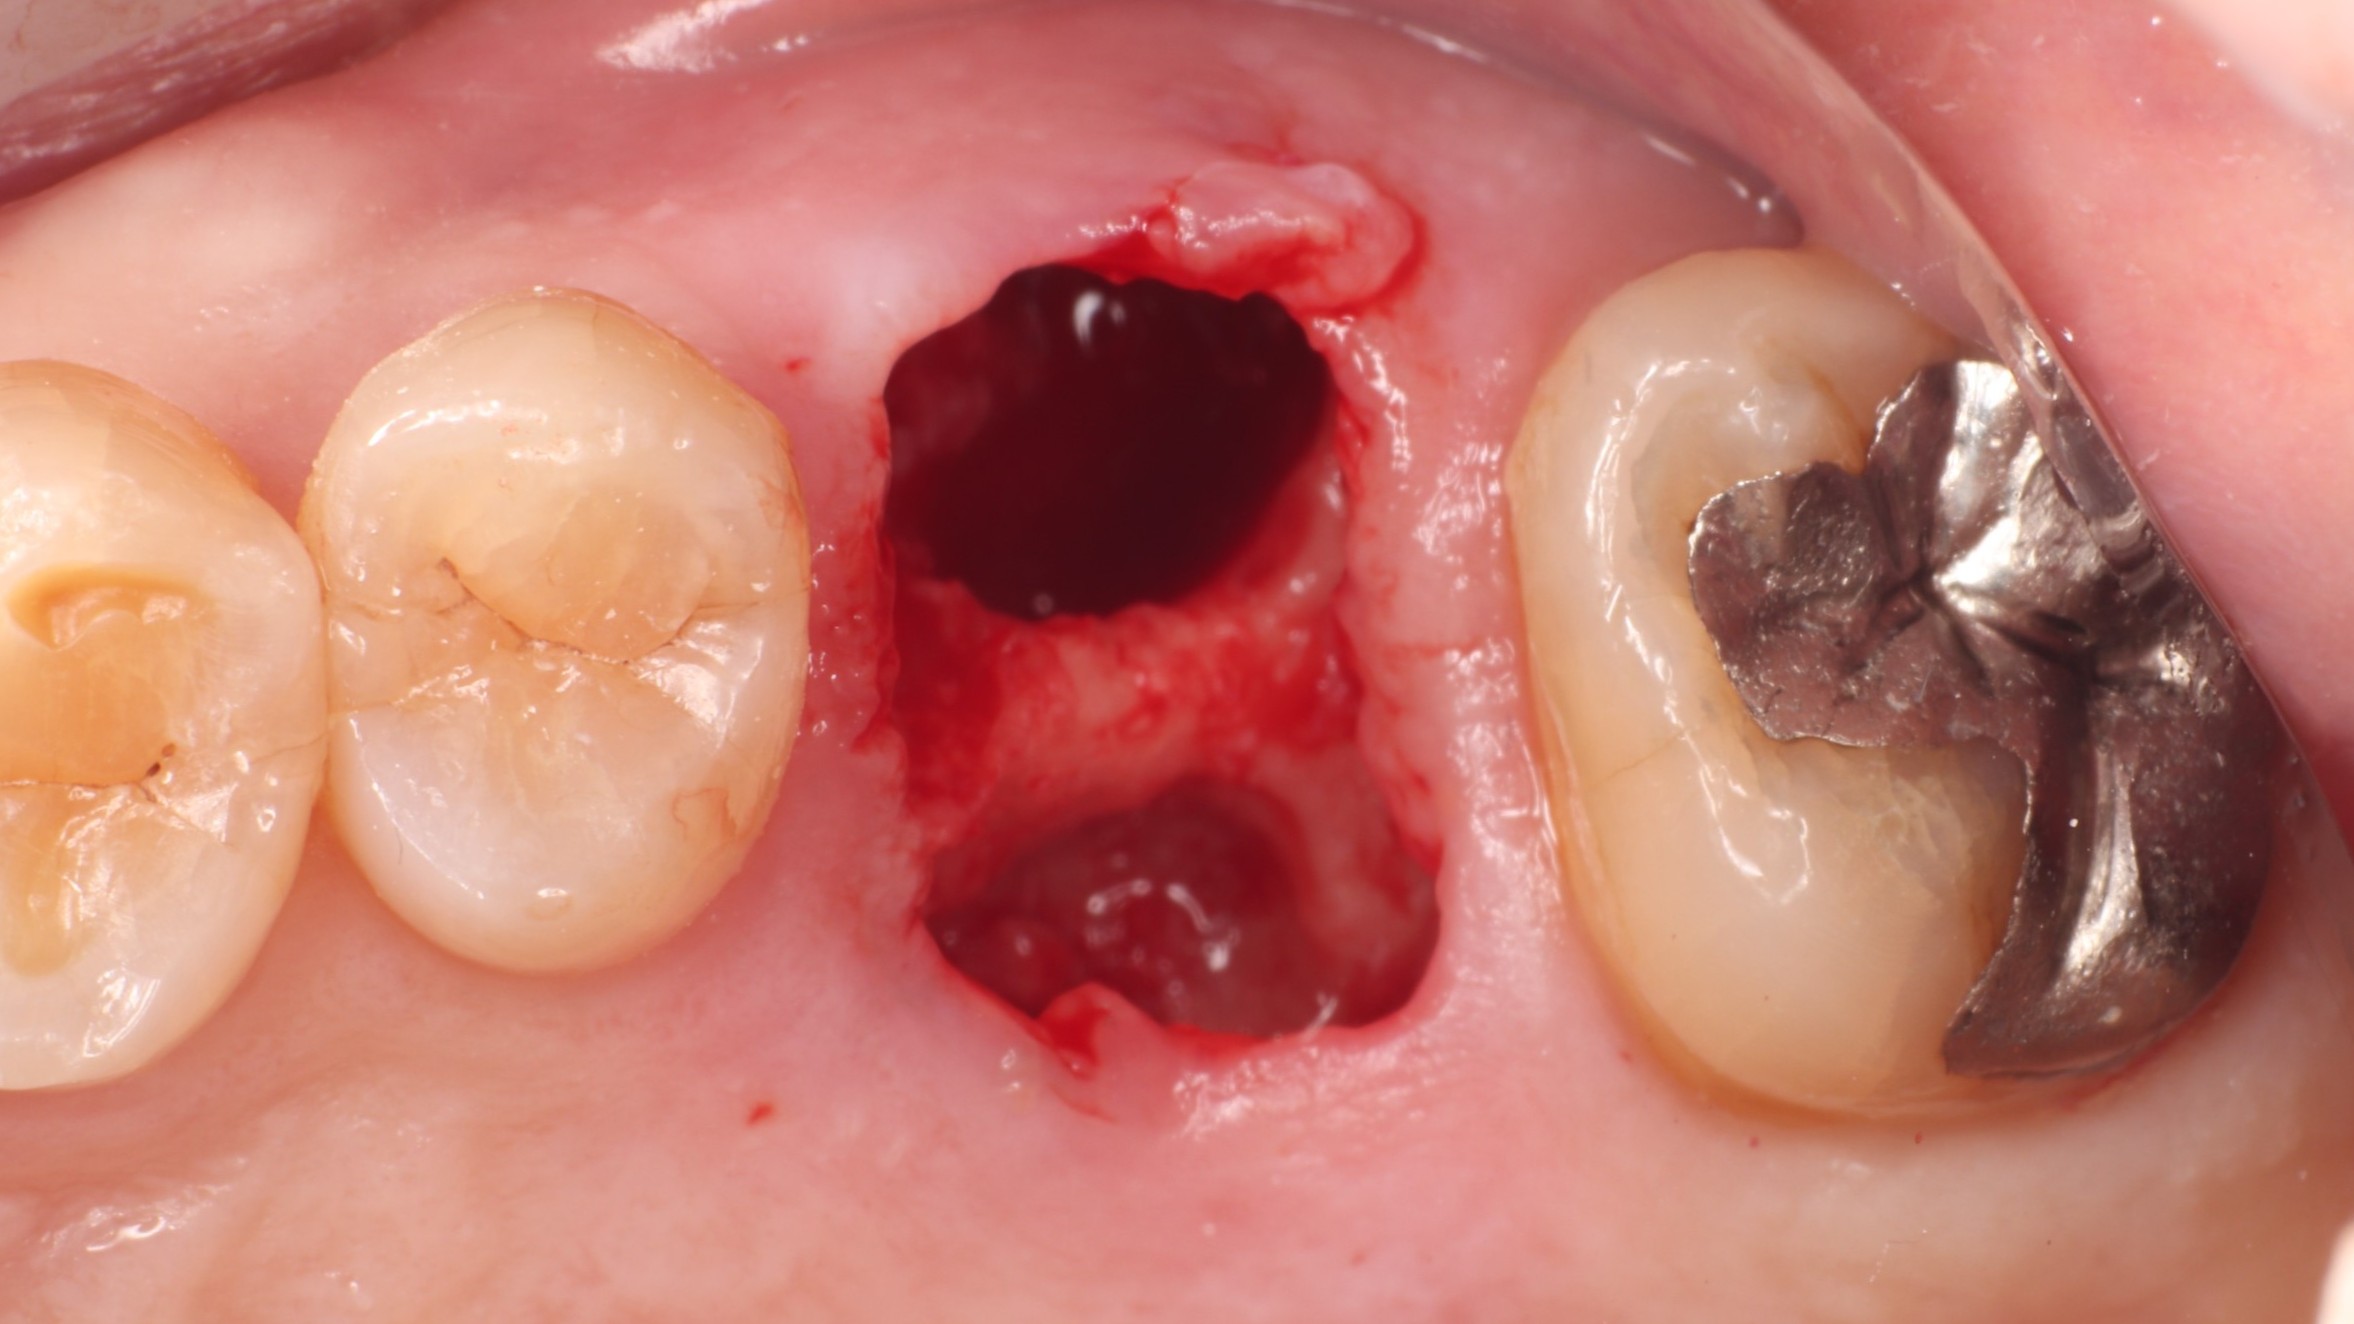

Step 2 抜歯直後

抜歯直後の抜歯窩

丁寧な抜歯処置により骨壁を温存。抜歯窩の形態を確認し、同日のインプラント埋入が可能と判断しました。切開・縫合の範囲を最小限に抑えることで、術後の腫れや痛みを軽減します。